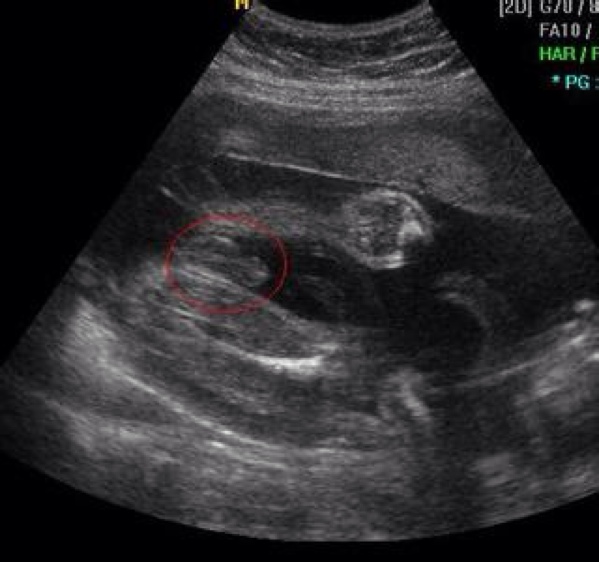

d.重点来啦,男宝和女宝,别说你不会看!